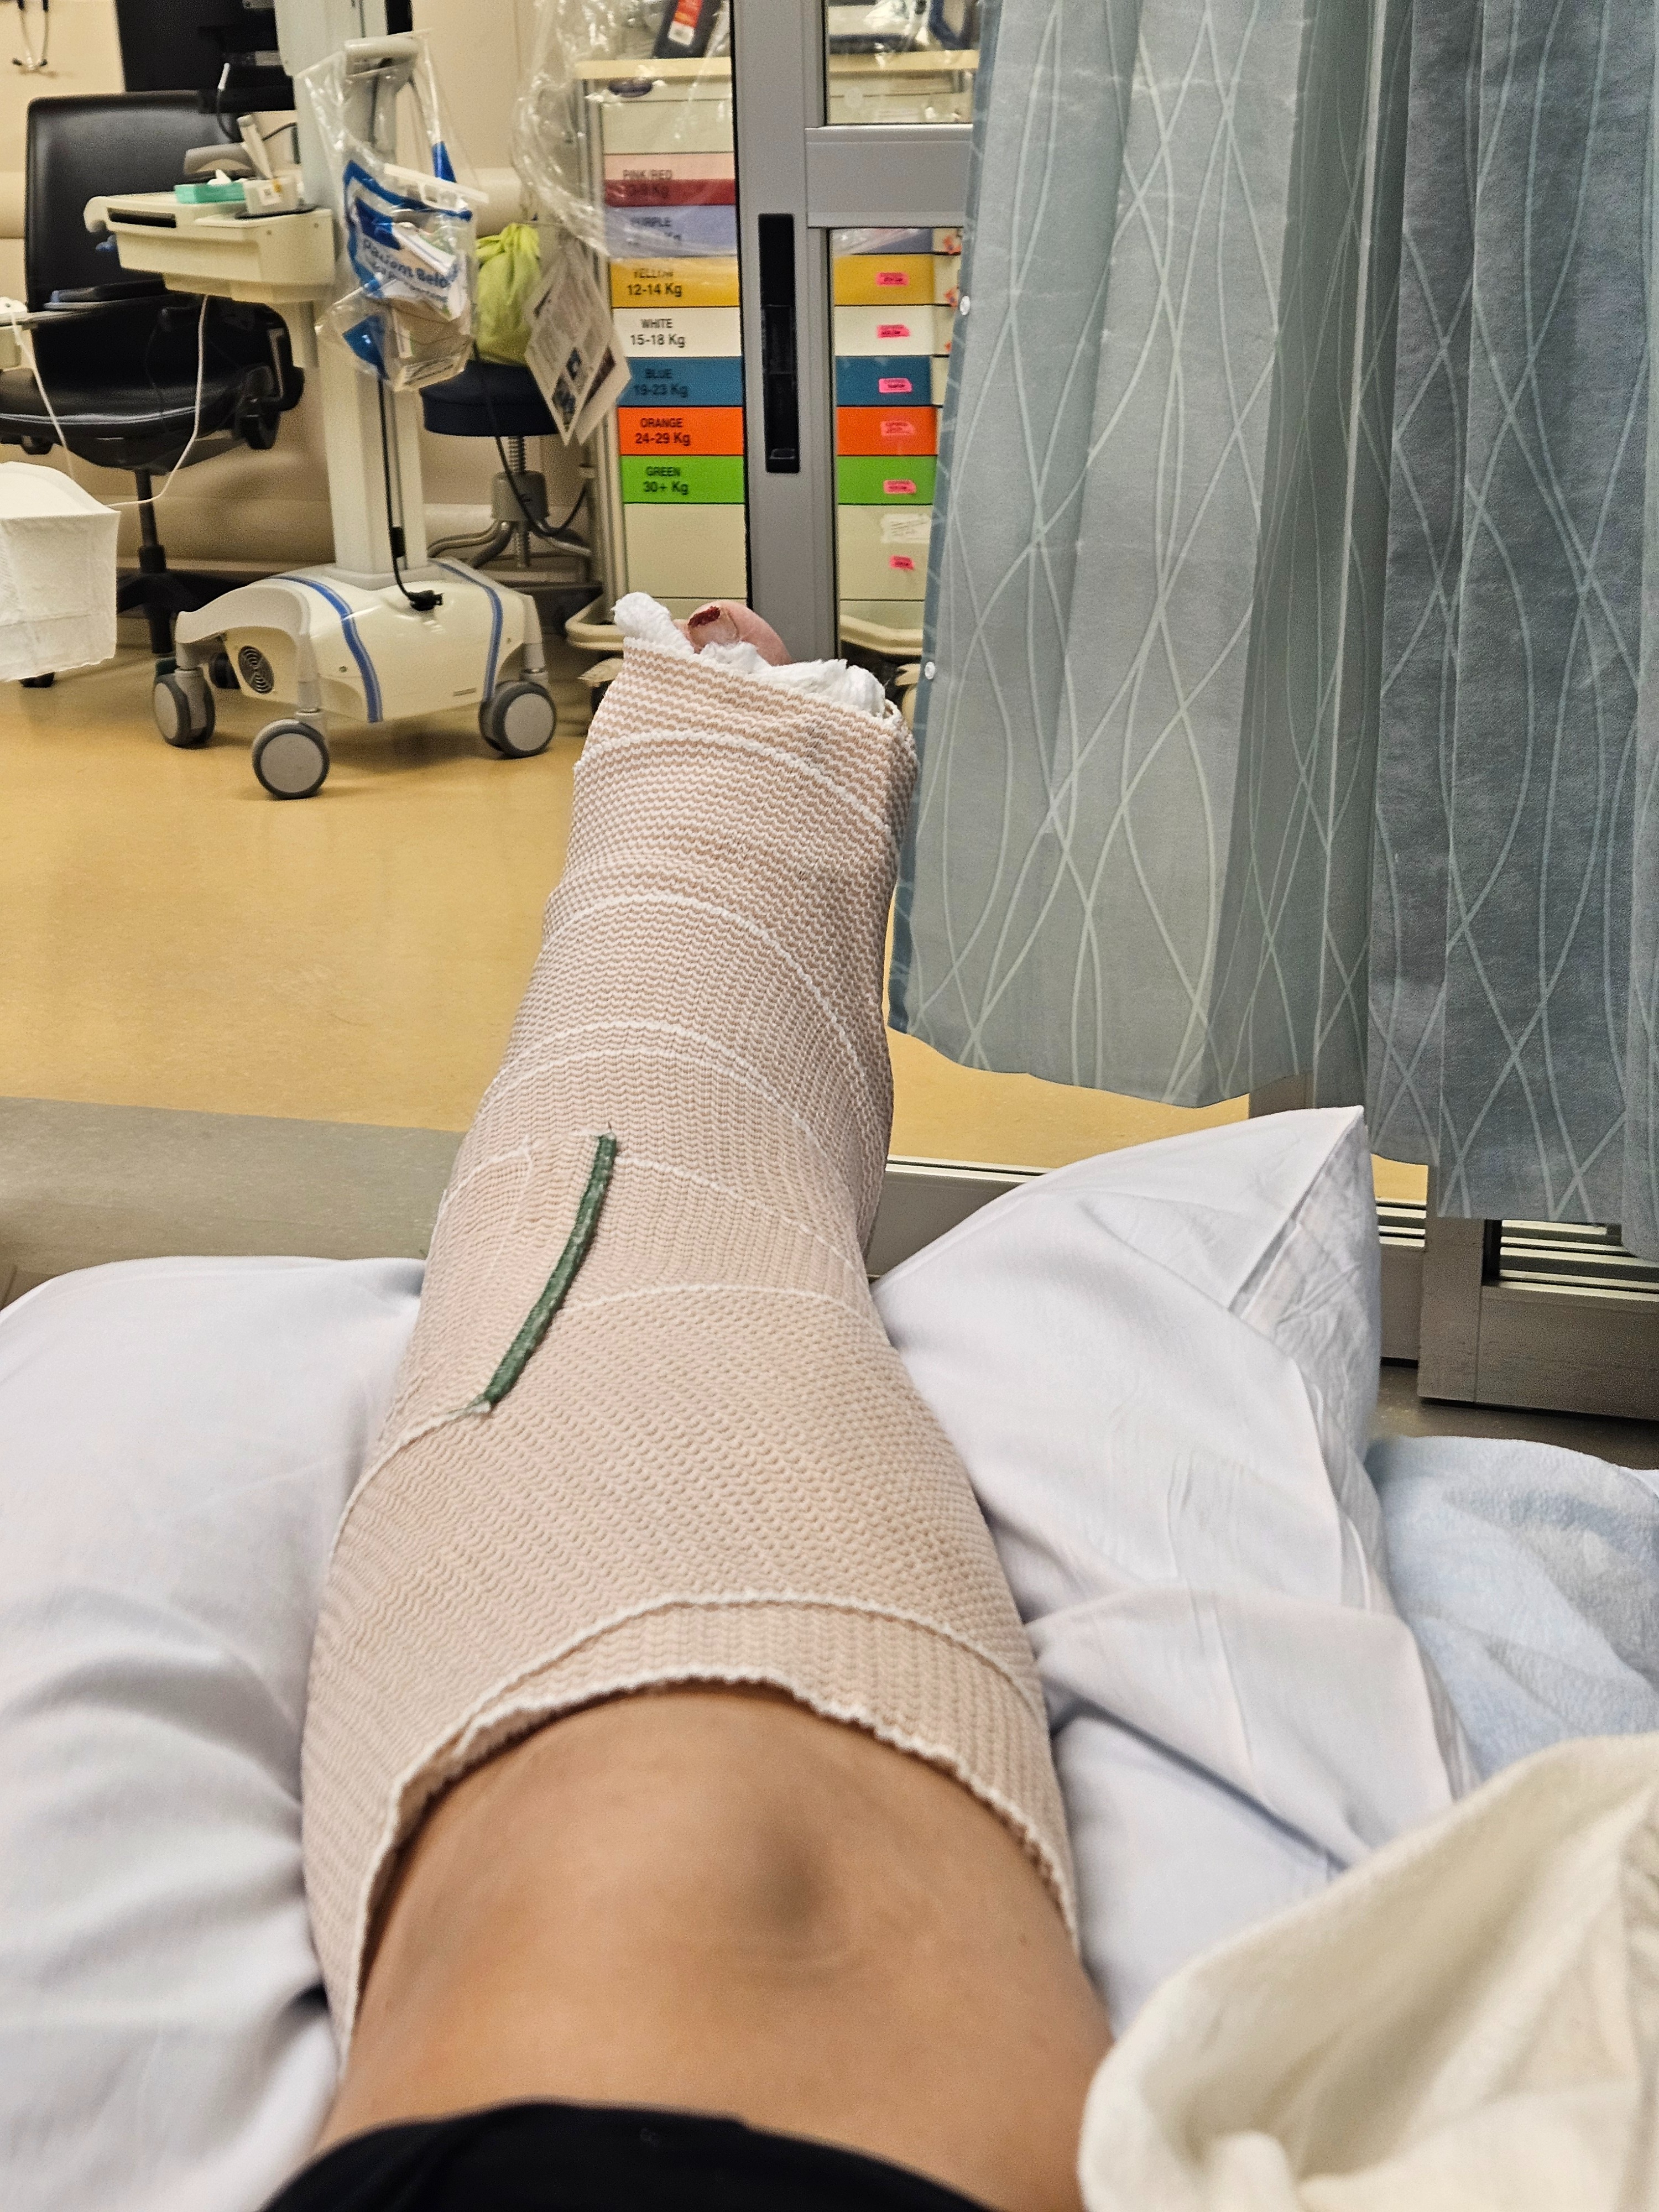

I stayed calm, and thankfully my family was there to help care for the kids while paramedics transported me by ambulance to the hospital. I spent the day in the ER, where I was placed in a soft cast and sent home with pain medication while awaiting surgery.

Surgery took place on January 2nd. Since then, recovery has been more challenging than expected. I am currently non-weight-bearing on my left ankle and must remain mostly flat with my leg elevated while my body heals. Pain management has been difficult, and day-to-day tasks require support.